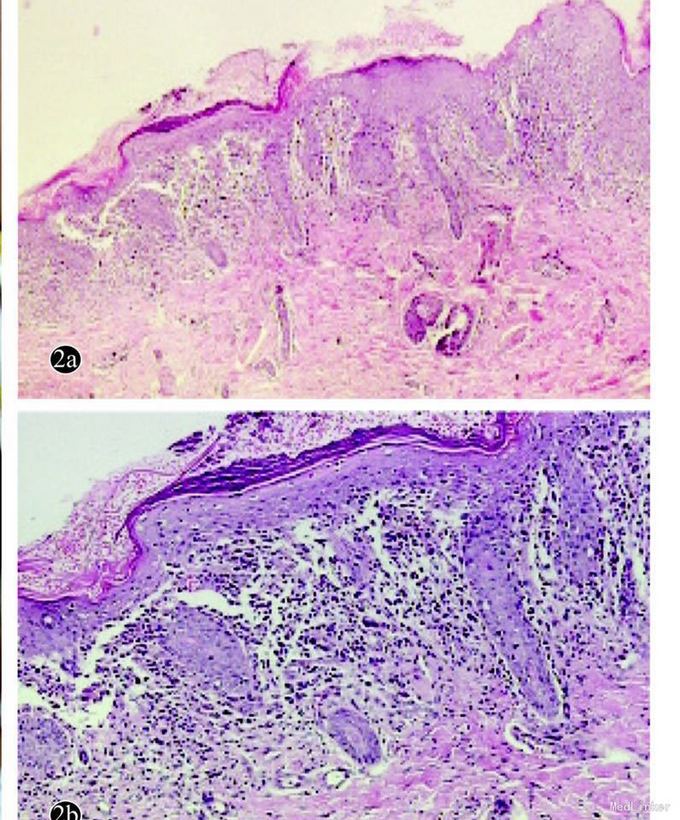

查体:全身皮肤干燥,可见散在或群集的淡红色丘疹,覆有棕黄色鳞屑,部分皮损痂可见皮消退后留有淡白色蜡样光泽扁平细小丘疹及斑疹。颅骨等未见缺损。 辅查:皮损病理见基底细胞液化变性,真皮乳头见组织细胞浸润。CD1a,S100,Cd68均阳性。胸腹Ct无异常。

诊断:朗格汉斯组织细胞增生症 处理:予外用康酸莫米松软膏及夫西地酸软膏涂抹患处。2周后复诊皮损基本消退。